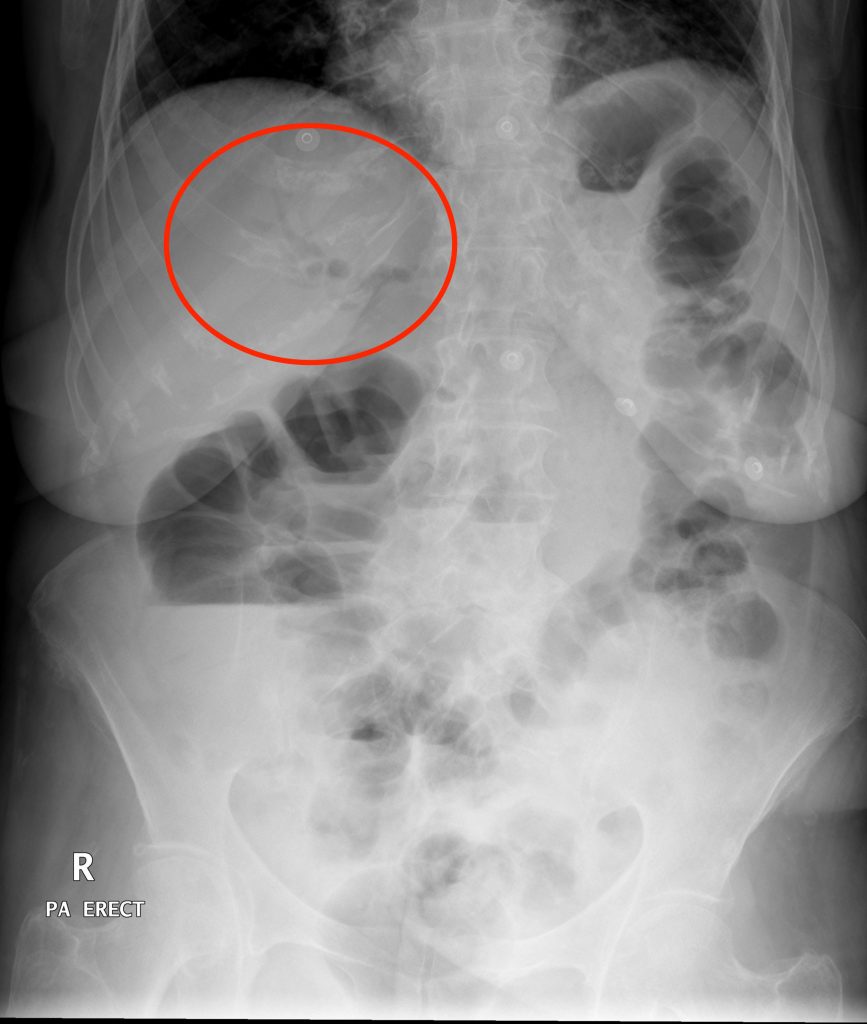

Labeled Kub X Ray Anatomy . Doctors can use it to help them. this article lists a series of labeled imaging anatomy cases by body region and modality. this involves assessment of the bowel gas pattern, soft tissue structures, and bones. This view is useful in assessing abdominal pathologies, including bowel obstructions, calcifications and neoplastic changes. Full assessment includes a check of.

This view is useful in assessing abdominal pathologies, including bowel obstructions, calcifications and neoplastic changes. this article lists a series of labeled imaging anatomy cases by body region and modality. this involves assessment of the bowel gas pattern, soft tissue structures, and bones. Doctors can use it to help them. Full assessment includes a check of.